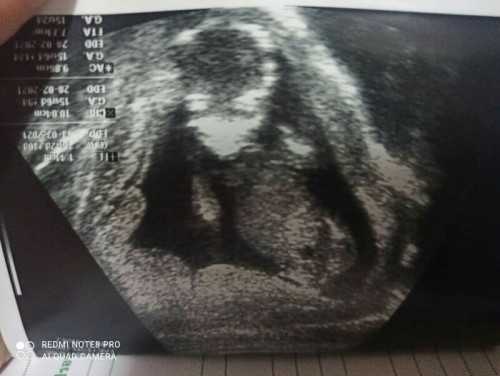

ท้อง 4 เดือน

ดิ้นเก่งมาก แต่ยังไม่รู้เพศนะคะ น้องปิดอย่างเดียวเลยค่ะ ลุ้นเพศมากค่ะ ช/ญ ตื่นเต้นจัง

บ้านนี้ซาวด์18สัปดาห์ โชว์ให้แม่ดูเลยค่ะ ได้ลูกสาว🥰